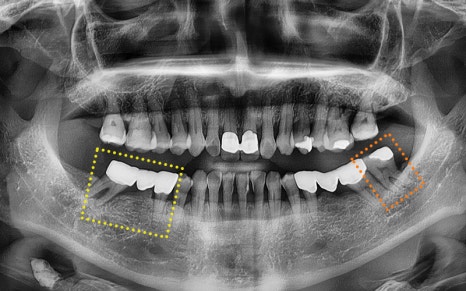

🦷 최종 계획

✔ 좌측 아래 사랑니

ㅡ> 감염 소견 있어 즉시 발치

✔ 우측 아래 기존 브릿지

ㅡ> 제거 후 발치 및 임플란트 식립 계획

최종적으로 크라운(보철물)까지 올려

치료를 성공적으로 마무리 해드렸답니다!

💕 전 > 후 💕

2025.02.13 ㅡ> 2025.06.11